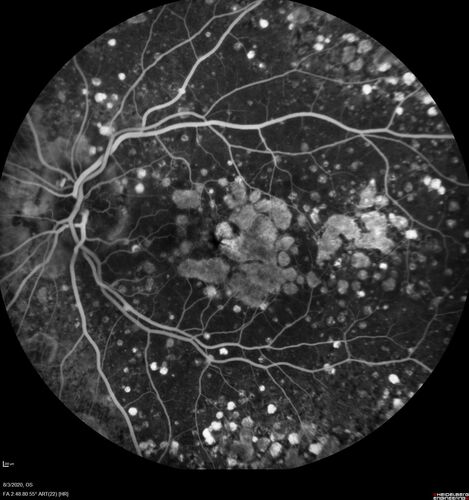

Age-related macular degeneration - Geographic Atrophy - Intermittent CME left eye from CRVO, Anemia, Diabetes

79 year old female - 3 years post CRVO in the left eye (20/32 VA) with intermittent CME.  Left eye is the better eye.  Vision is stable since 2 years ago

PMHx: Type II DM x 20 years, Chronic Anemia, Hyperlipidemia

VA 20/200 OD, 20/50 OS (usually 20/40)